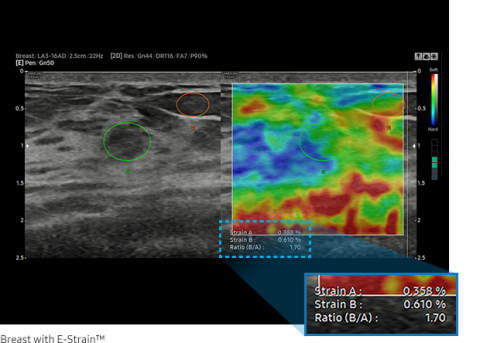

E-Strain™ is designed to enable quick and easy calculation of the strain ratio between two regions of interest for day-to-day practice. Simply by setting the two targets, you can receive accurate, onsistent results and make informed decisions in many types of diagnostic procedures.